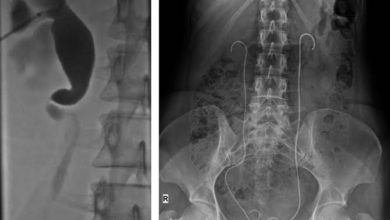

Böbreğe Takılan Çift J (Double J) Stentler Hakkında Bilgi

Double J stent nedir? Bilindiği gibi böbreklerimiz belimizin her iki yanında bulunan ve kanı süzerek idrar üreten organlarımızdır. İdrar torbamız…